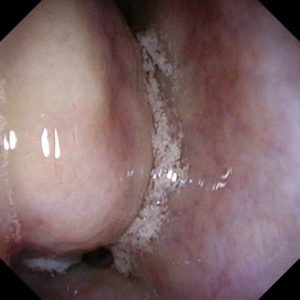

- Cancerous lumps/ Sinonasal tumors: Occasionally, some lumps in the nose are due to cancers. There can be several different types and only a biopsy can confirm the diagnosis. Picture below shows a patient diagnosed with a melanoma within the nasal cavity (Fortunately a rare condition). Find out more about sinonasal tumors here https://my.clevelandclinic.org/health/diseases/17477-sinonasal-tumors.